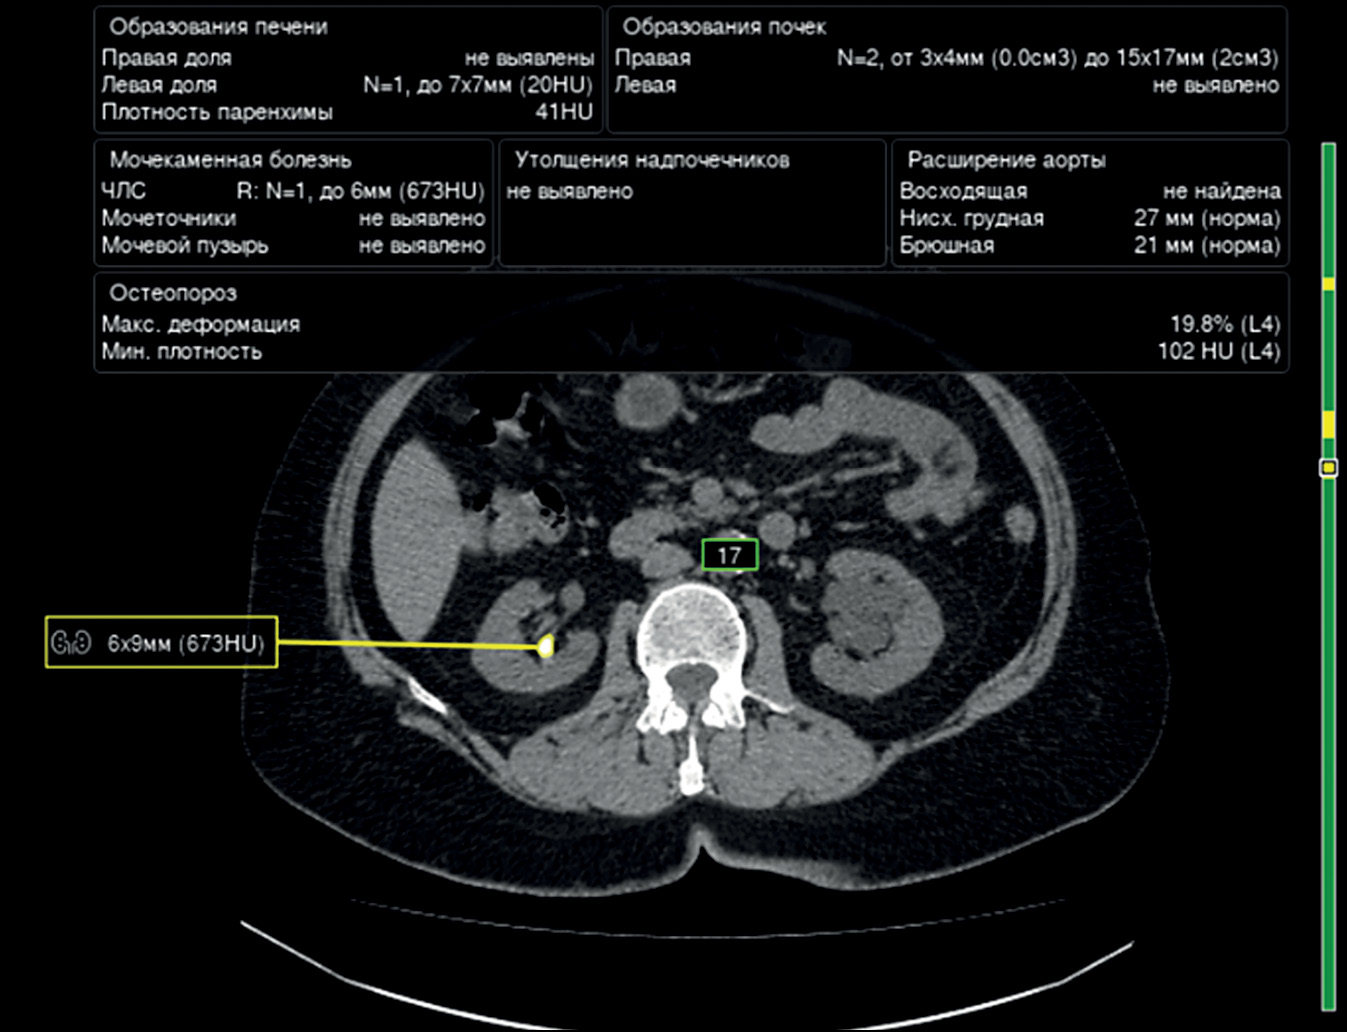

The articles showed a direct association between the accuracy of urinary stone detection and the size of urinary stones. The accuracy of convolutional neural network-based algorithms increases with the size of urinary stones [35, 36]. To illustrate, the accuracy rates of detecting urinary stones <1 , 1–2 , and >2 cm were 85%, 89%, and 93%, respectively.

The Swin transformers algorithm has currently the greatest accuracy in urinary stone detection (98%) [29]. An example of urinary stone detection using one of the algorithms is presented in Fig. 4.

Fig. 4. An example of urinary stone detection using one of the algorithms.

The use of computer vision algorithms for the diagnosis of urinary stone diseases can be challenging if small atherosclerotic plaques are present in renal artery walls because their densities are similar to those of urinary stones [36].

Modern deep machine-learning and computer vision technologies allow for the detection of urinary stones measuring ≥3 mm with low radiation exposure, and urinary stones measuring ≥5 mm are considered clinically significant [37].